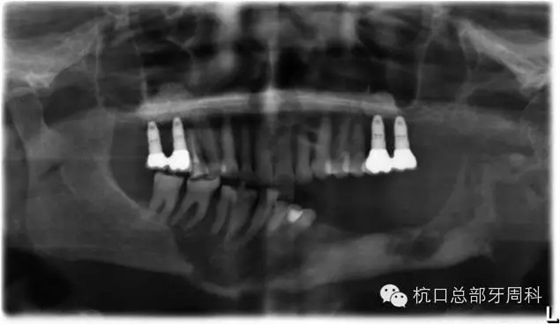

種植后即刻拍片 2005

被診斷為種周炎時全景片 2011